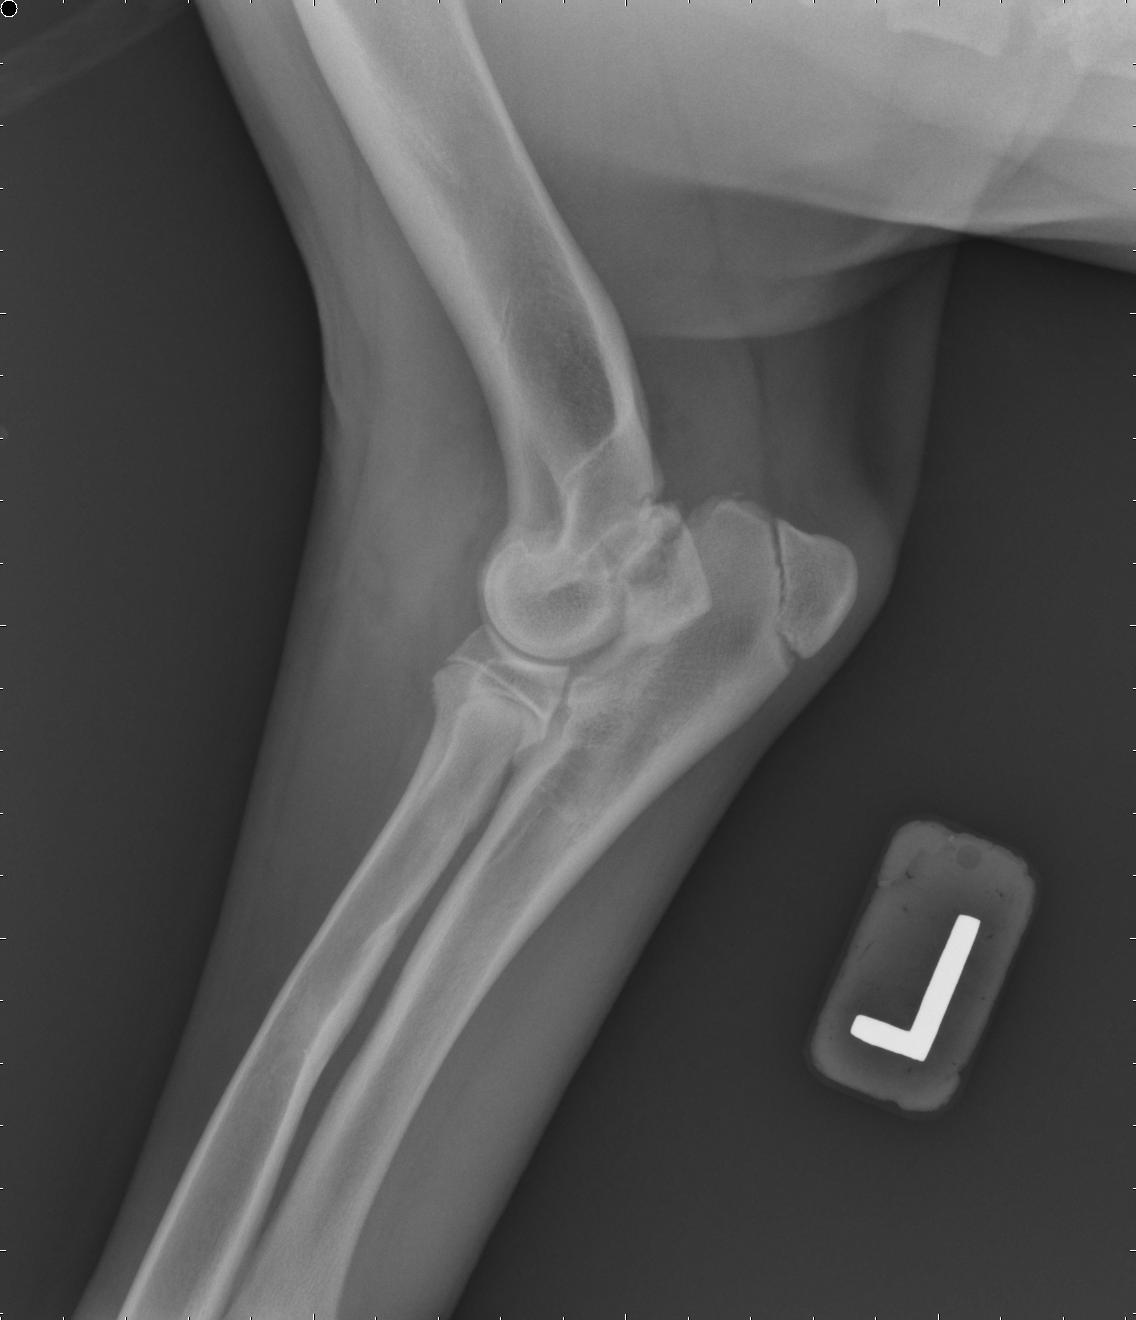

Shoulder_OCD0001 Shoulder_OCD0002

Above are x-rays of a left and right shoulder affected with OCD lesions. These are on the same patient. The images labeled with the left (L) marker has a flattened region noted by the arrow which is characteristic of OCD. The image on the right has the area highlighted in blue. While the lesion doesn’t look big, it can definitely cause a lot of pain and discomfort.